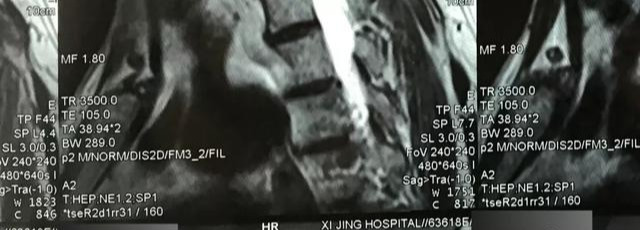

12.拍摄时,请尽可能清楚地获取胶卷上的文字信息,然后在左右拍摄(胶片上有一个标记,指示右侧和L,指示左侧的左侧)。如图16和图17所示,图18中的r,可以根据阅读习惯正确拍摄每部胶片上的文本,并且不会错误地拍摄(图21-4,图22)。

(图21-4)

这张照片是图21中完整的磁共振膜上拍摄的部分照片。拍摄时,您必须以正确的方向专注于胶片上的文字,并使文本清晰可见(图22),并保留尽可能多有关电影的信息。

(图22)

图21-4图片上的放大屏幕截图的文本清晰可见